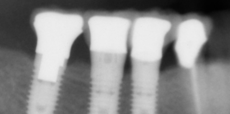

Single Implant - Case 5